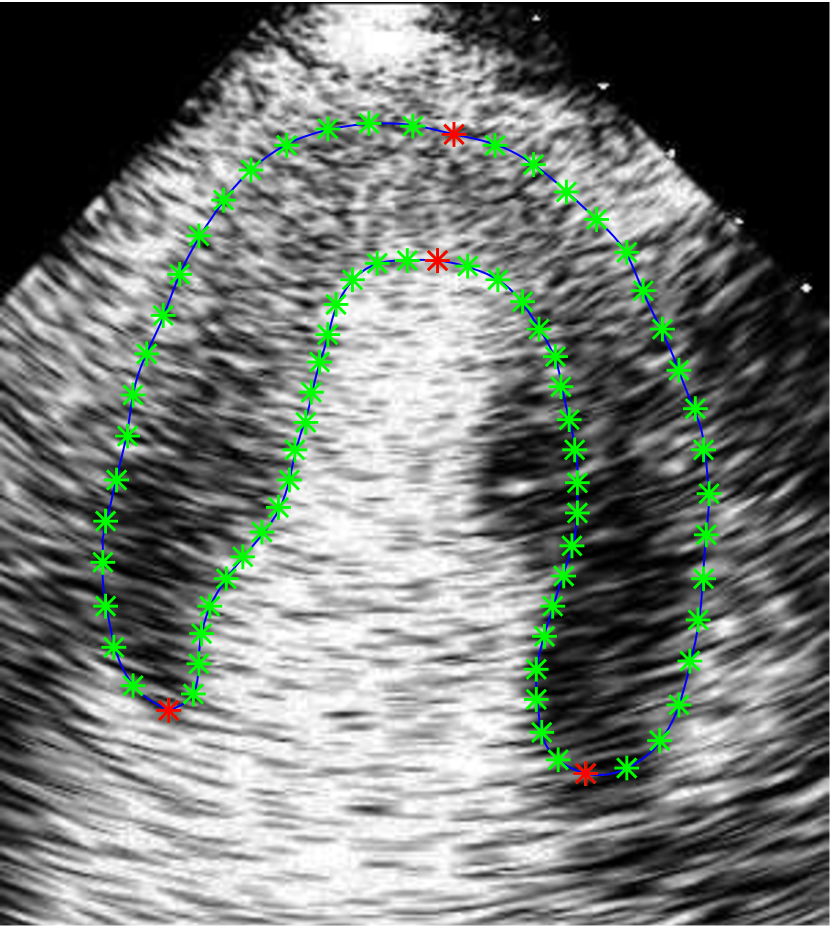

Refer to caption

(a)

(b)

(c)

Figure 2: (a) Manual annotations showing key landmarks in red and other landmarks in green. (b) First and second modes of variation of the shape model with bisubscript𝑏𝑖b_{i} varying in the range of ±2λiplus-or-minus2subscript𝜆𝑖\pm 2\sqrt{{\lambda}_{i}}. (c) SM feature computation. Left: Landmarks 𝒙𝒙\boldsymbol{x} generated randomly by the shape model in (1) (blue dots). Right: SM feature values d1subscript𝑑1d_{1} and d2subscript𝑑2d_{2} measure the signed shortest distance from boundary B𝐵B (blue contour) to pixel 𝒑𝟏subscript𝒑1\boldsymbol{p_{1}} and 𝒑𝟐subscript𝒑2\boldsymbol{p_{2}} respectively. d1subscript𝑑1d_{1} is positive and d2subscript𝑑2d_{2} is negative.

III-B Shape Model Construction

In this section, we explain the construction of a statistical shape model of the myocardium which is required for the subsequent stages of our segmentation pipeline. Statistical shape model is extremely useful for representing objects with complex shapes. It captures plausible shape variations while removing variations due to noise. The 2D myocardial shape can be effectively represented using the point distribution model [24] which uses a set of landmarks to describe the shape. The model is built from a set of training shapes using PCA which captures the correlations of the landmarks among the training set. Each training shape is defined by a set of M𝑀M landmarks. It consists of 4 key landmarks with the other landmarks uniformly sampled in between (Fig. 2(a)). The key landmarks are the two apexes on the epicardium and endocardium and the two endpoints on the basal segments. The point distribution model is given by:

Manual annotations for the two datasets are done by an expert. For Dataset1𝐷𝑎𝑡𝑎𝑠𝑒𝑡1Dataset1, each image is manually annotated with a bounding box which encloses the myocardium. This is used for training and testing the CNN. A myocardial contour is also manually delineated for each image in Dataset1𝐷𝑎𝑡𝑎𝑠𝑒𝑡1Dataset1 and for every image of the 12 sequences in Dataset2𝐷𝑎𝑡𝑎𝑠𝑒𝑡2Dataset2. This is used for training and testing the RF. Subsequently, 4 key landmarks are manually identified on the myocardial contour as illustrated in Fig. 2(a). 18 landmarks are uniformly sampled in between each pair of key landmarks to give a total of M𝑀M=76 landmarks that define each myocardial shape. The landmark annotations are used for shape model construction.